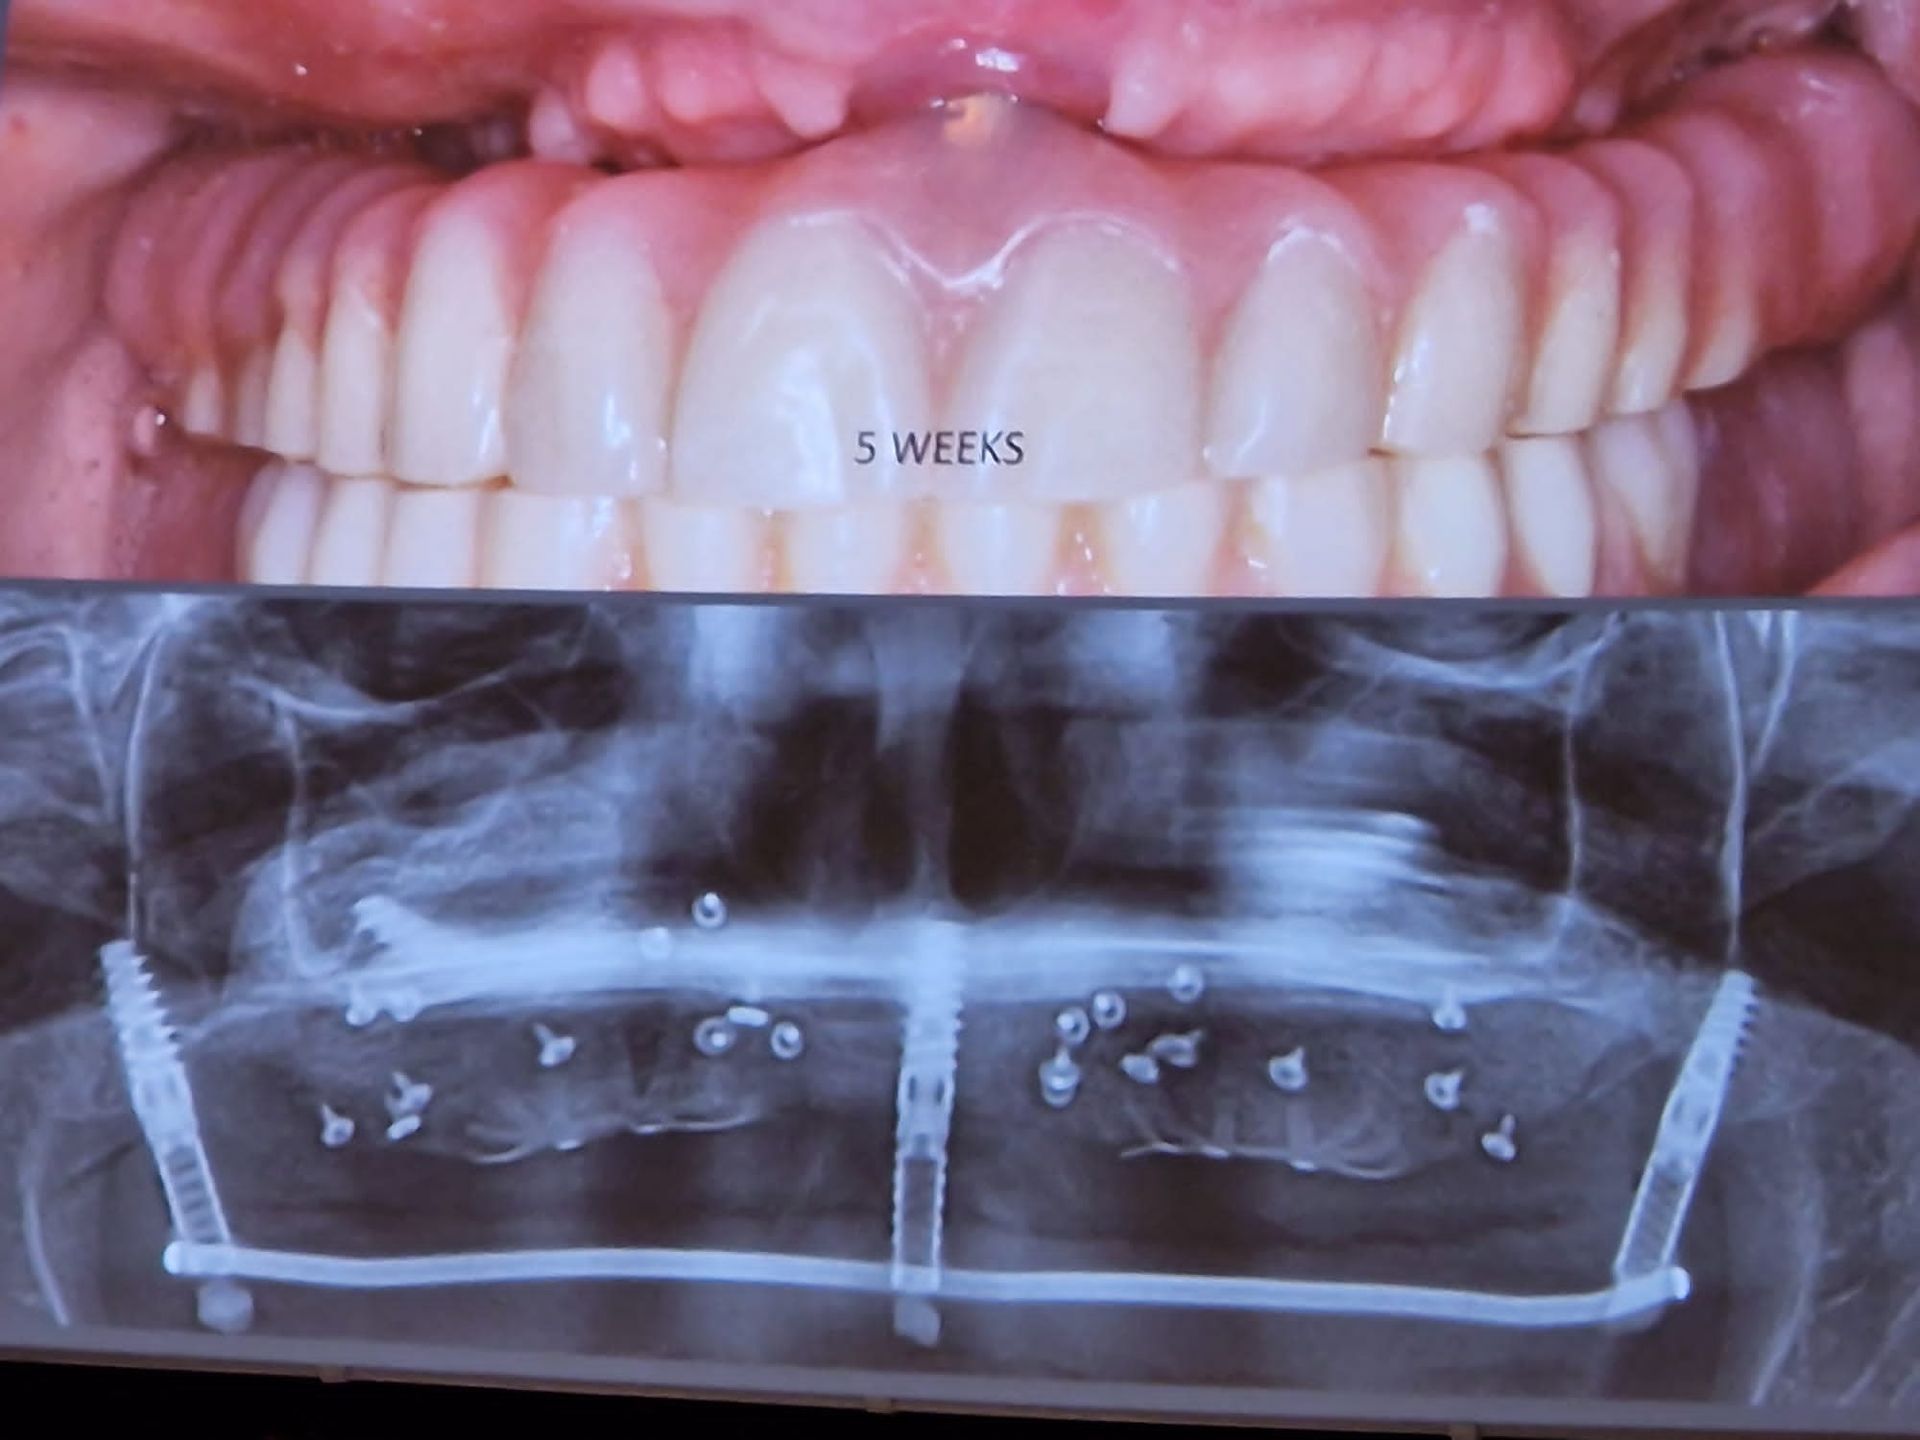

Inoltre consigliamo controlli frequenti e periodici associati a detartrasi annuale e, quando necessario, trattamenti dentistici su misura, come lo sbiancamento con laser odontoiatrico, la cura delle malattie gengivali, l'applicazione di faccette in ceramica e le terapie di ortodonzia con apparecchio dentale.